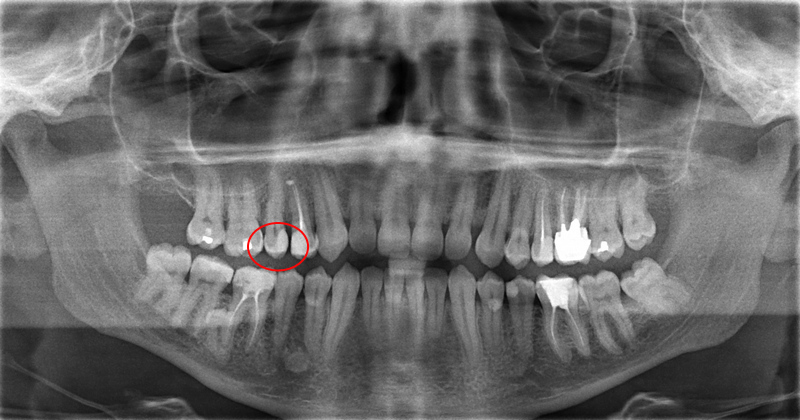

Дентальные снимки и диагностика кариеса